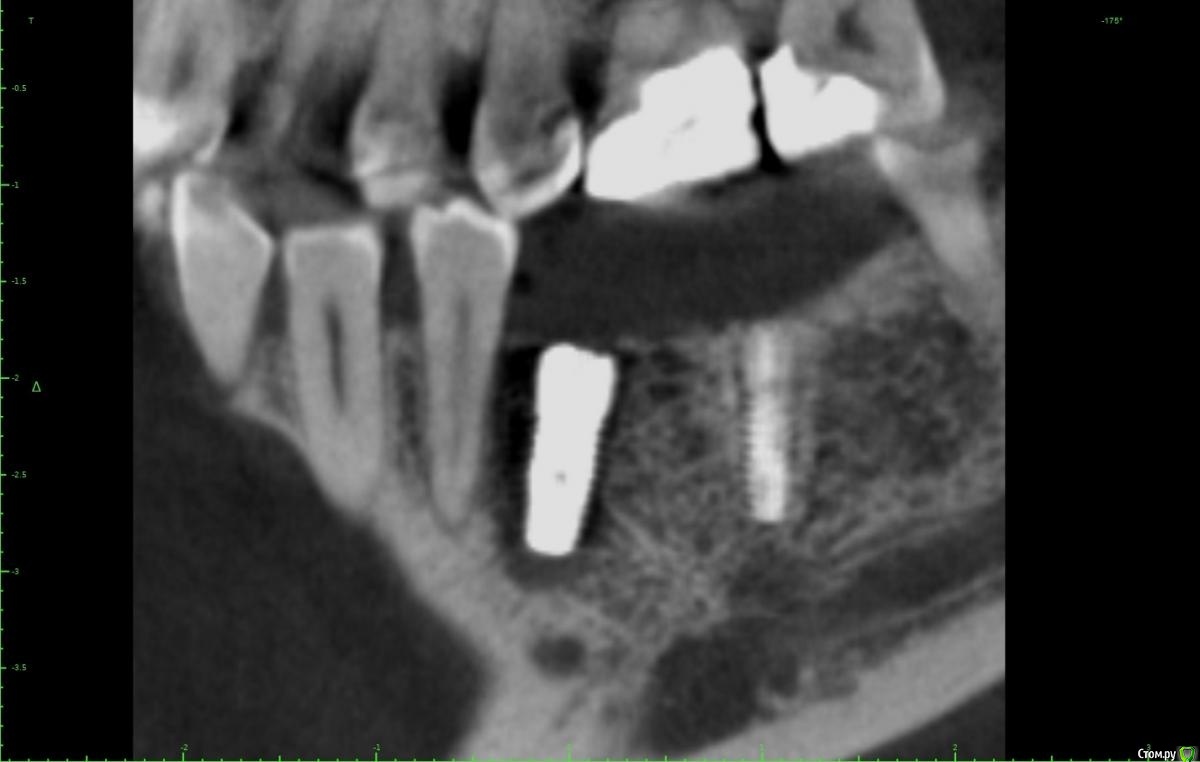

Женька Опубликовано 28 ноября, 2020 Поделиться Опубликовано 28 ноября, 2020 (изменено) Приветствую коллеги. В общем три недели назад 07.11.20 установил пациентке 2 имплантата в позиции 45-46. Гребень по ширине был около 6.5мм в области 4.5 и около 7.2мм в области 4.6 (с учётом заглубления на 1.5-2мм). Это была наверное первая имплантация во время которой я чувствовал себя спокойно и расслабленно. Всё прошло хорошо, немного покопался с непосредственным введением имплантатов, тк никак не хотели топиться на нужные 1.5мм. Поэтому пробовал методику с выкручиванием на пару витков и снова закручиванием. Особого толку не получил, потому взял финальную фрезу и чуть углублял ложе. Так несколько раз, тк боялся всё-таки немного что задену менталис и нлн. Ввиду того, что биотип у пациентки тончайший и язычно было совсем-совсем тонко - заглушки и швы. Назначил нпвс, ванны хг, аб терапию. Но на утро следующего дня пациентка сказала, что чувствует себя шикарно, решили что нпвс оставим, а аб терапию применять не будем (и грешу что в этом мою ошибка).Через неделю сняли швы, всё отлично.Спустя два дня после снятия начались какие-то "костные" боли, как говорит пациентка в области 4.5 импланта. Которые то отпускают, то снова наплывают. На 4.4 есть дефект твердых тканей (на фото виден), но судя по всему беспокоит не он .Пальпация вестибулярно в проекции 4.5 импланта болезненна, небольшая гиперемия, отёка нет. Гигиену пациентка запустила, тк боялась туда залезать и чистить. Снимки прилагаю первые два от 07.11, два последующих 28.11. Ну и внутри ротовые день операции и сегодняшние числа.Похоже 4.5 на выход? своими "туда-сюда" наверняка я нагрел всё что можно... снова расстройство в той работе, где накосячить предельно сложно... Добавка: пить аб ведь сейчас уже бесполезно? Изменено 28 ноября, 2020 пользователем Женька Ссылка на комментарий

Женька Опубликовано 14 декабря, 2020 Автор Поделиться Опубликовано 14 декабря, 2020 (изменено) Наконец-то получил КТ от пациентки...Боли значительно уменьшились, практически не беспокоит... Коллеги, что думаете? Я так понимаю это уже не фон от титана? и вердикт всё-таки один? Сам склоняюсь всё-таки более к понаблюдать. Вестибулярно конечно очень тонко Толщина была ~ 6.7мм Изменено 14 декабря, 2020 пользователем Женька Ссылка на комментарий

Irouil Опубликовано 14 декабря, 2020 Поделиться Опубликовано 14 декабря, 2020 Ну и где тут язычно передавленная кортикалка? Меня смущает только картина в области верхушки симптомного винта, ну и заглубление Я бы дождался уже срока интеграции Ссылка на комментарий

Женька Опубликовано 14 декабря, 2020 Автор Поделиться Опубликовано 14 декабря, 2020 Ну и где тут язычно передавленная кортикалка? Меня смущает только картина в области верхушки симптомного винта, ну и заглублениеНе знаю, я про язычную кортику не говорил. Меня тоже смущает... и в области соседа такого фона (а это не фон я уверен) нет... А с заглублением что не так? по прицелам там 1.5-2мм, на кт почему-то этих мм вообще нет и как будто крестально стоят Ссылка на комментарий